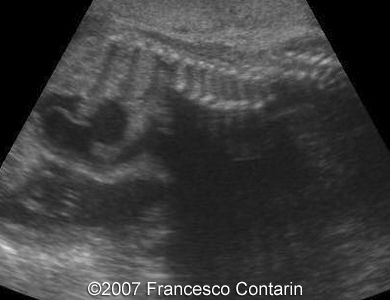

This is a 22-year-old woman (G4, P2) with unremarkable familiar history, referred to our hospital at 29 weeks of gestation due to a fetal ascites. There were no signs of maternal-fetal blood incompatibility. The ultrasound investigation revealed rhizomelia, postaxial polydactyly, small thorax, short ribs, ascites, increased abdominal biometric parameters, polyhydramnios. We supposed two diagnoses: Short rib-polydactyly syndrome versus Jeune syndrome (asphyxiating thoracic dystrophy).

Images 3, 4. 29th week of pregnancy -  shortened tibia (left); and polydactyly of the hand (right).

3

4